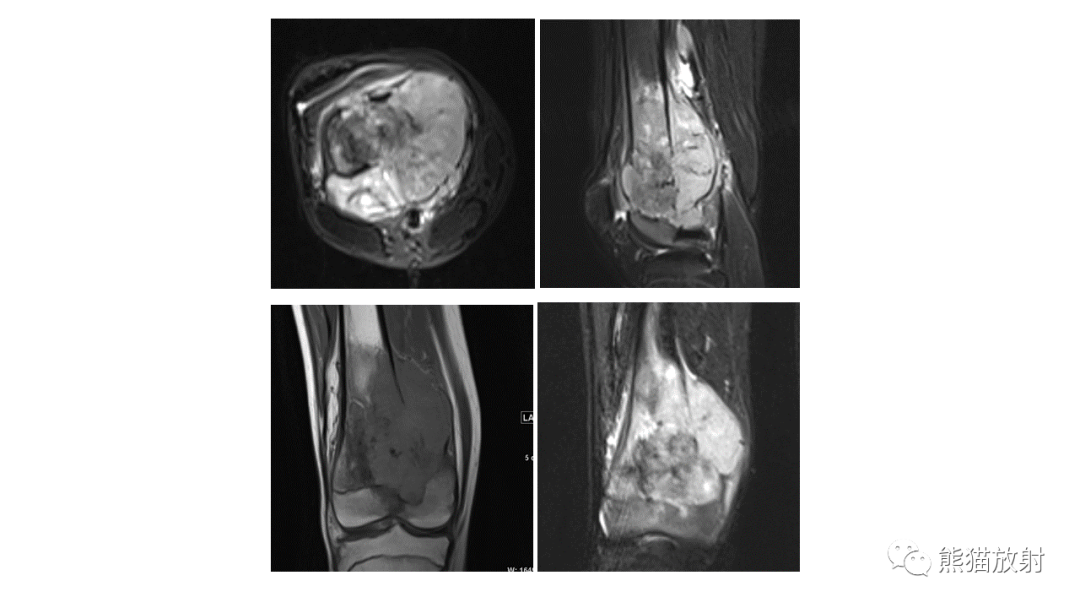

股骨淋巴瘤 VS 股骨转移瘤